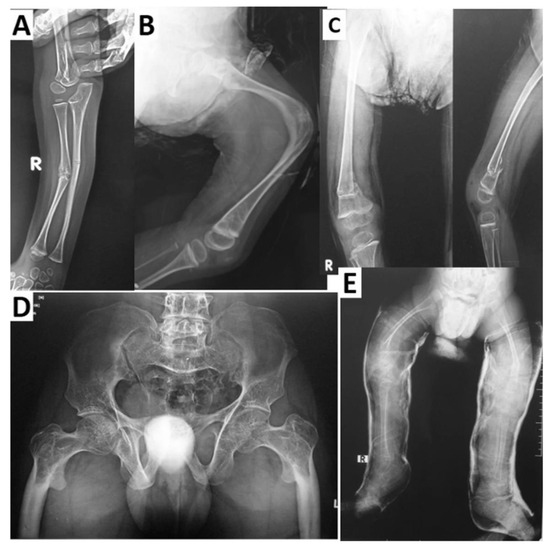

- Littman, J.; Phornphutkul, C.; Saade, C.; Katarincic, J.; Aaron, R. Osteoporosis, Fractures, and Blindness Due to a Missense Mutation in the LRP5 Receptor. Orthop. Res. Rev. 2023, 15, 39–45. [Google Scholar] [CrossRef] [PubMed]

- Zhao, D.; Sun, L.; Zheng, W.; Hu, J.; Zhou, B.; Wang, O.; Jiang, Y.; Xia, W.; Xing, X.; Li, M. Novel mutation in LRP5 gene cause rare osteosclerosis: Cases studies and literature review. Mol. Genet. Genomics. 2023, 298, 683–692. [Google Scholar] [CrossRef]